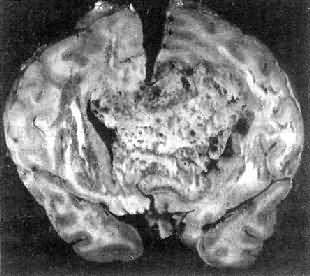

图16-23 星形胶质细胞瘤 左大脑半球肿胀,肿瘤边界不清,部分呈胶冻状 镜下,肿瘤细胞形态多样,可相似于纤维型星形胶质细胞、原浆型星形胶质细胞和肥胖星形胶质细胞,故分别称为纤维型、原浆型和肥胖型星形胶质细胞瘤。前二者为良性肿瘤,后者性质介于良恶性之间。如肿瘤细胞出现间变,细胞密度增大,异型性明显,核深染,出现核分裂像,毛细血管内皮细胞增生,则为间变性星形胶质细胞瘤,为恶性肿瘤。 高度恶性的星形胶质细胞瘤称为多形性胶质母细胞瘤(glioblastoma multiforme),多见于成人。肿瘤好发于额叶、颞叶白质,浸润范围广,常可穿过胼胝体到对侧,呈蝴蝶状生长(图16-24)。瘤体因常有出血坏死而呈红褐色。镜下,细胞密集,异型性明显,可见怪异的单核或多核瘤巨细胞。出血坏死明显,是其区别于间变性星形胶质细胞瘤的特征。毛细血管明显增生,内皮细胞增生、肿大,可导致管腔闭塞和血栓形成。肿瘤发展迅速,预后极差,患者多在2年内死亡。

图16-24 多形性胶质母细胞瘤 发生于儿童、青少年的毛发细胞型星形胶质细胞瘤,生长极为缓慢。有报道称患者在不完全切除肿瘤后有带瘤存活达40年者。该瘤常位于小脑、第四脑室底部、第三脑室、丘脑和视神经。其形态特点是由双极性的肿瘤细胞两端发出纤细的毛发状突起。即使有毛细血管增生,本瘤的预后仍相对较好。 应该指出,同一肿瘤的不同区域,瘤细胞可有不同的形态特征,且分化程度也不尽相同,因此肿瘤的分型仅具有相对的意义。 星形胶质细胞瘤的细胞骨架含有胶质纤维酸性蛋白(GFAP),免疫组织化学染色呈阳性反应,是该肿瘤的特异标志。 2.少突胶质细胞瘤(oligodendroglioma) 约占颅内胶质瘤的5%,主要见于30~40岁的成人,男女发病的机会相等。本瘤绝大部分位于大脑半球皮质的浅层,尤以左额叶为多见。 肉眼观,肿瘤呈灰红色边界清楚的球形肿块,位于白质和邻近的皮质,并可累及软脑膜。囊性变、出血和钙化颇为常见,其中钙化灶对X线诊断有一定帮助。 镜下,瘤细胞大小均匀,形态单一,弥漫排列,胞核居中着色深,胞浆空,环绕胞核形成空晕。间质富有血管,有不同程度的内皮细胞增生。约有20%病例可出现瘤细胞钙化,其范围大小不一,其中7%为镜下钙化,有时钙化灶较大,可在X线片上显示出来。如肿瘤组织中混有星形胶质细胞瘤成分达到50%,则称混合性少突星形胶质细胞瘤。 本瘤生长缓慢,病程可长达10~30年,临床表现多为癫痫和局部性瘫痪。少数生长迅速,酷似多形性胶质母细胞瘤,预后不佳。 3.室管膜(细胞)瘤(ependymoma)起源于室管膜细胞,患者多为儿童和青少年。本瘤占颅内胶质瘤的5%~6%,多见于第四脑室,其次为侧脑室、第三脑室和导水管。脊髓病变多发生于腰胝及马尾部。 肉眼观,颅内室管膜瘤呈膨胀性生长,边界清楚,呈球形、分叶状或乳头状,肿瘤多在脑室内生长。切面灰白色,呈均匀或颗粒状,可发生灶性出血甚至坏死或囊性变,有时也可发现点状钙化。 镜下,瘤细胞大小形态一致,呈梭形或胡萝卜形,胞核圆或椭圆,染色质呈细颗粒状,核膜清楚,有核仁。瘤细胞胞浆丰富,突起明显。瘤细胞的排列有二种特征,一是环绕空腔排列成腺管状,形态上与室管膜腔相似,称为菊形团形成,另一是环绕血管形成假菊形团结构,瘤细胞有细长的胞浆突起与血管壁相连(图16-25)。细胞中有神经胶质纤维,以PTAH染色在个别细胞的腔面或胞核旁可见纤毛体,后者与纤毛运动有关,是室管膜细胞的特征性结构。此外,有时还可形成乳头状结构。发生在脊髓圆锥和终丝的肿瘤,乳头状结构轴心中的结缔组织往往富含粘液。